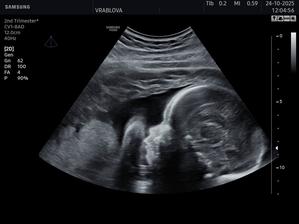

Samko 🩵🤰🏻

Z tejto lásky sa nám čoskoro narodí náš lásky kvet 🥹💓